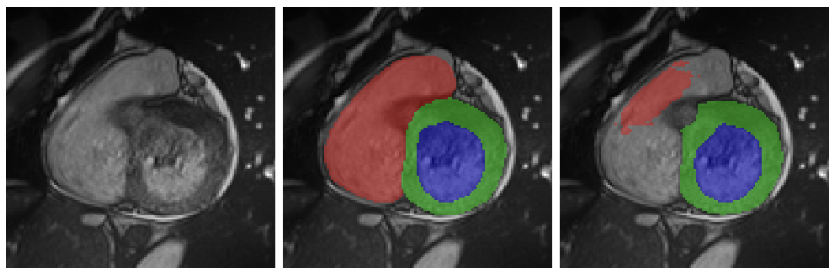

Deep Learning Techniques for Automatic MRI Cardiac Multi-Structures Segmentation and Diagnosis: Is the Problem Solved?

Olivier Bernard, Alain Lalande, Clement Zotti, Frederick Cervenansky, Xin Yang, Pheng-Ann Heng, Irem Cetin, Karim Lekadir, Oscar Camara, Miguel Angel Gonzalez Ballester, Gerard Sanroma, Sandy Napel, Steffen Petersen, Georgios Tziritas, Elias Grinias, Mahendra Khened, Varghese Alex Kollerathu, Ganapathy Krishnamurthi, Marc-Michel Rohé, Xavier Pennec, Maxime Sermesant, Fabian Isensee, Paul Jäger, Klaus H. Maier-Hein, Peter M. Full, Ivo Wolf, Sandy Engelhardt, Christian F. Baumgartner, Lisa M. Koch, Jelmer M. Wolterink, Ivana Išgum, Yeonggul Jang, Yoonmi Hong, Jay Patravali, Shubham Jain, Olivier Humbert, Pierre-Marc Jodoin

IEEE Transactions on Medical Imaging, 37, 2514-2525 (2018)

journal URL

An exploration of 2D and 3D deep learning techniques for cardiac MR image segmentation

Christian F. Baumgartner, Lisa M. Koch, Marc Pollefeys, Ender Konukoglu

International Workshop on Statistical Atlases and Computational Models of the Heart, 111--119 (2017)

preprint URL